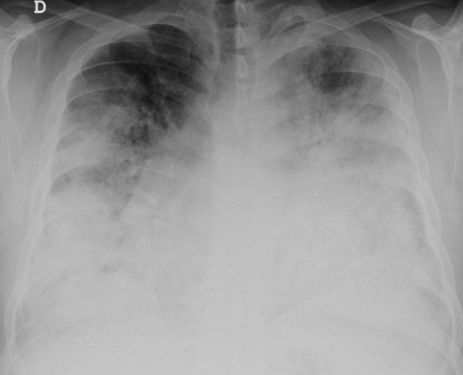

Boala legionară este o infecție pulmonară gravă cauzată de bacteria Legionella pneumophila. Aceasta se transmite prin inhalarea de vapori sau aerosoli de apă contaminată, provenind de obicei din sisteme de climatizare, turnuri de răcire sau fântâni decorative. Simptomele includ febră, frisoane, tuse, dificultăți de respirație și, în cazuri severe, pneumonie.